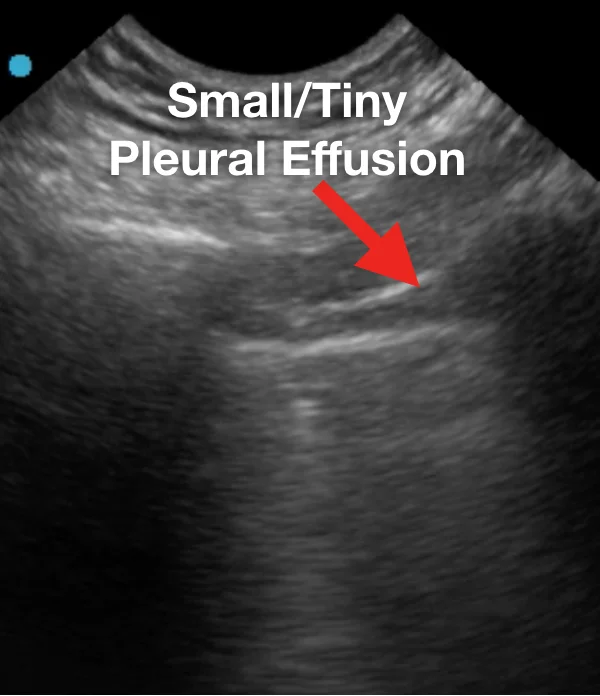

Характерные выводы включают следующее:

Наблюдаемые паттерны происходили в промежутке от легкого альвеолярного интерстициального паттерна до тяжелого двустороннего интерстициального паттерна и консолидации легких. В таблице 1 приведены типичные результаты УЗИ легких у пациентов с респираторным заболеванием COVID-19 в сравнении с данными КТ грудной клетки.

Ниже представлен ряд изображений патологических изменений, которые Вы можете увидеть при УЗИ легких пациентов с COVID-19. Эти изменения можно найти в любой части легкого, поскольку COVID-19 имеет мультифокальное распределение. Возможно сочетание областей нормального легкого и области с патологией. Патологические изменения легких могут отсутствовать в начале заболевания и при легком течении COVID-19, однако, по мере его прогрессирования, Вы можете наблюдать всё больше патологических изменений.

Ниже приведены примеры УЗ-картины легких пациентов с COVID-19.